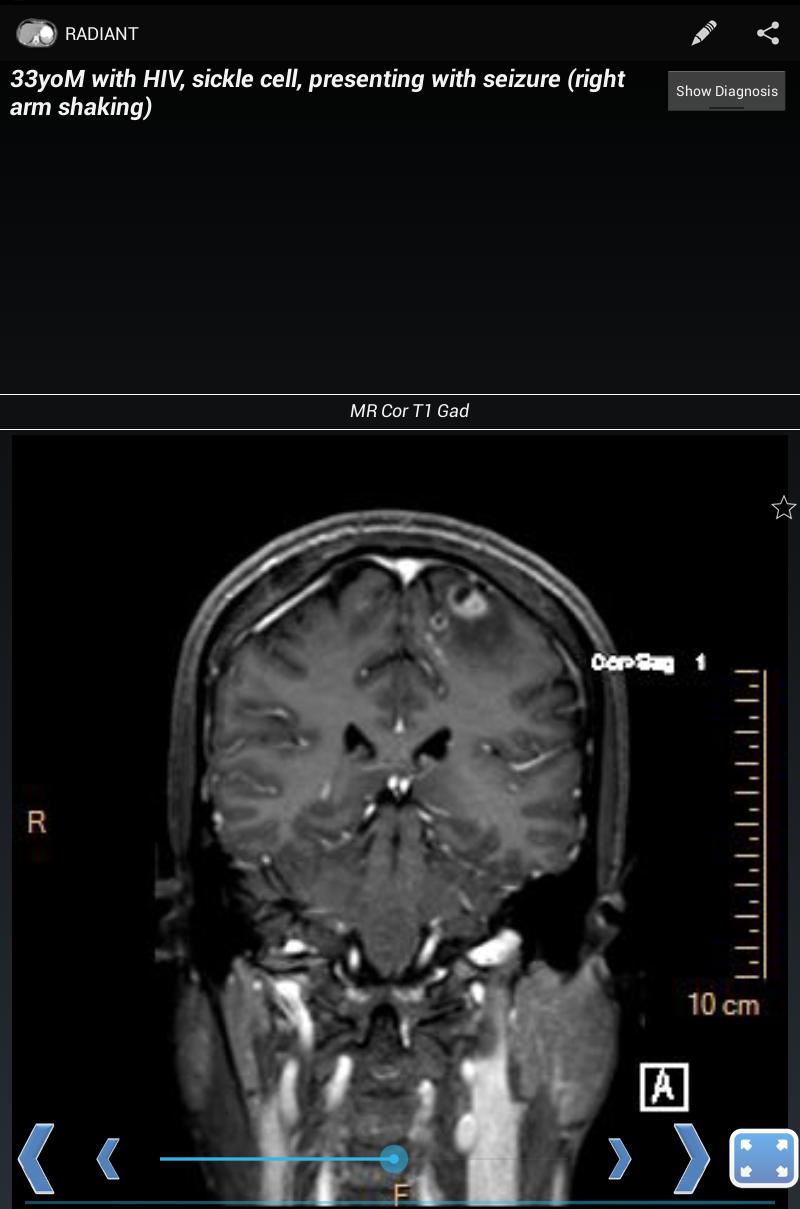

Create, view, and share interactive, image-based radiology education content

RADIANT is a platform to create, manage, and share image-based educational materials, primarily intended for users in the medical field. It is ideal for sharing interesting cases among diagnostic radiology residents, fellows, medical students, and faculty. It is NOT meant to be used for diagnosis.

With RADIANT, you can create cases showing x-rays, ultrasound, CT, MRI, or any other imaging modality. It is a great way to learn chest x-rays, normal anatomy, and common disease processes, using real, high-quality diagnostic medical images.